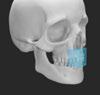

que comprometan el resultado final (Figura 32). La irrupción de las nuevas tecnologías también ha permitido al campo de la regeneración ósea guiada incrementar la precisión de los procedimientos que se realizan. Gracias a radiografías 3D y escaneados intraorales se están diseñando guías quirúrgicas para realizar los cortes óseos que permiten extraer los bloques óseos autólogos con una mayor precisión y reduciendo drásticamente el riesgo de complicaciones (De Stavola y cols 2015; De Stavola y cols 2017). Adicionalmente, no solo para la obtención de bloques óseos sino también para la fijación y estabilización de láminas ya sean autólogas o no, también se están diseñando guías quirúrgicas que permiten al clínico incrementar la seguridad de procedimientos tan sensibles como estos (Ortiz-Puigpelat y cols 2024).